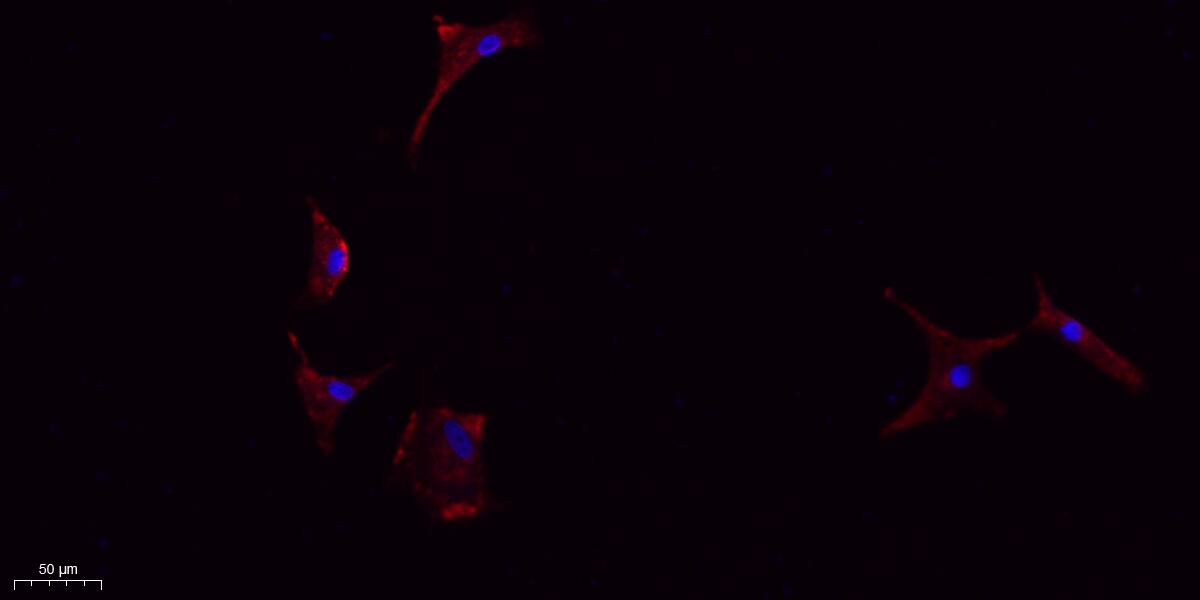

Immunofluorescence analysis of A549.

IF 1:100-300